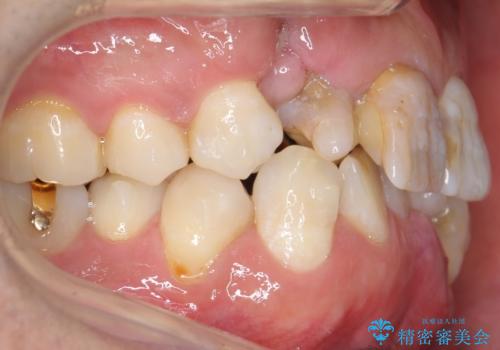

歯並びにより、そのままだときれいに被せ物をいれられない状態でした。

重度の叢生(歯並びのがたがた)のため、

患者様の「できるだけ短期間で治療を終わらせたい、セラミックが入れられたら良いので大がかりなことはしたくない」とのご要望により、3Dシミュレーションを何度も行い患者様とのコンサルを重ね、上顎左右犬歯と左下2を抜歯して②のプランである補綴前矯正(インビザライン)を行うことにしました。

仕上がりに限界はありましたが、比較的短期間で歯並びが整いセラミック治療を行うことができ、患者様に「治療して良かった」とご満足頂けました。

右上21:ジルコニアクラウン スペシャル

左上6:ジルコニアクラウン スタンダード

左上7:e-max press セラミックインレー